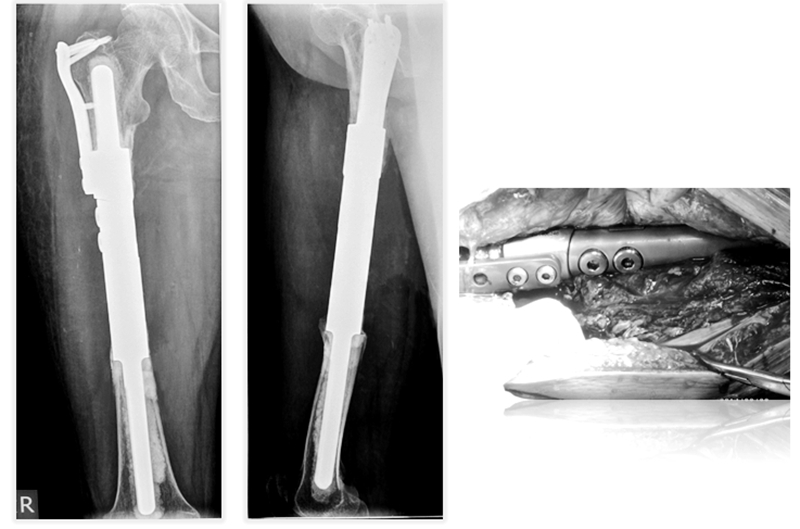

为进一步解决骨干肿瘤诊治中的难题,胡永成教授通过多年临床研究,终于设计出“骨干组配式假体”,该技术通过较小的创伤便可使患者得到好的治疗效果。除此之外,胡永成教授还根据骨干肿瘤发病部位的不同进行分区,根据不同的损伤部位可以进行个性化假体的选择,不仅可以帮助患者保留关节,患者术后还能即刻下地,大大减轻了肿瘤患者的痛苦,并提高了生存质量。

病例分享

患者女性,68岁,乳腺癌病史,右股骨中段病理性骨折,股骨长段溶骨性破坏,并有跳跃病灶。病变的长度为16cm,病灶近端在小转移水平,因为近端髓腔柄较短,故选择A区骨干假体。经病理诊断为转移性腺癌,术后2周患者拆线后即可离床活动。